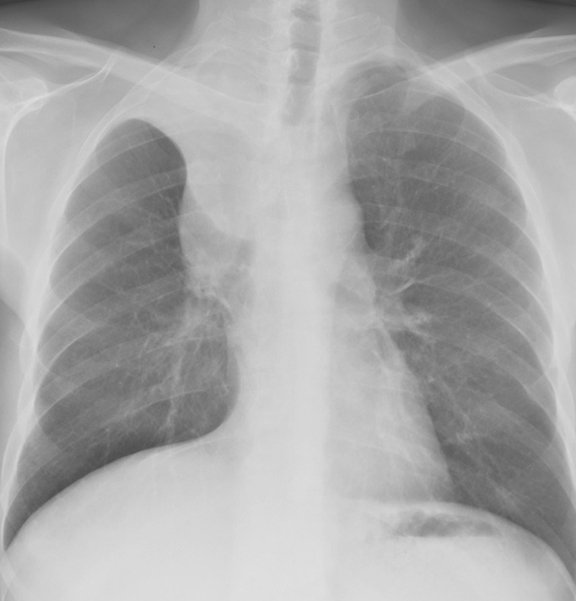

RUL Collapse Case 4 PA